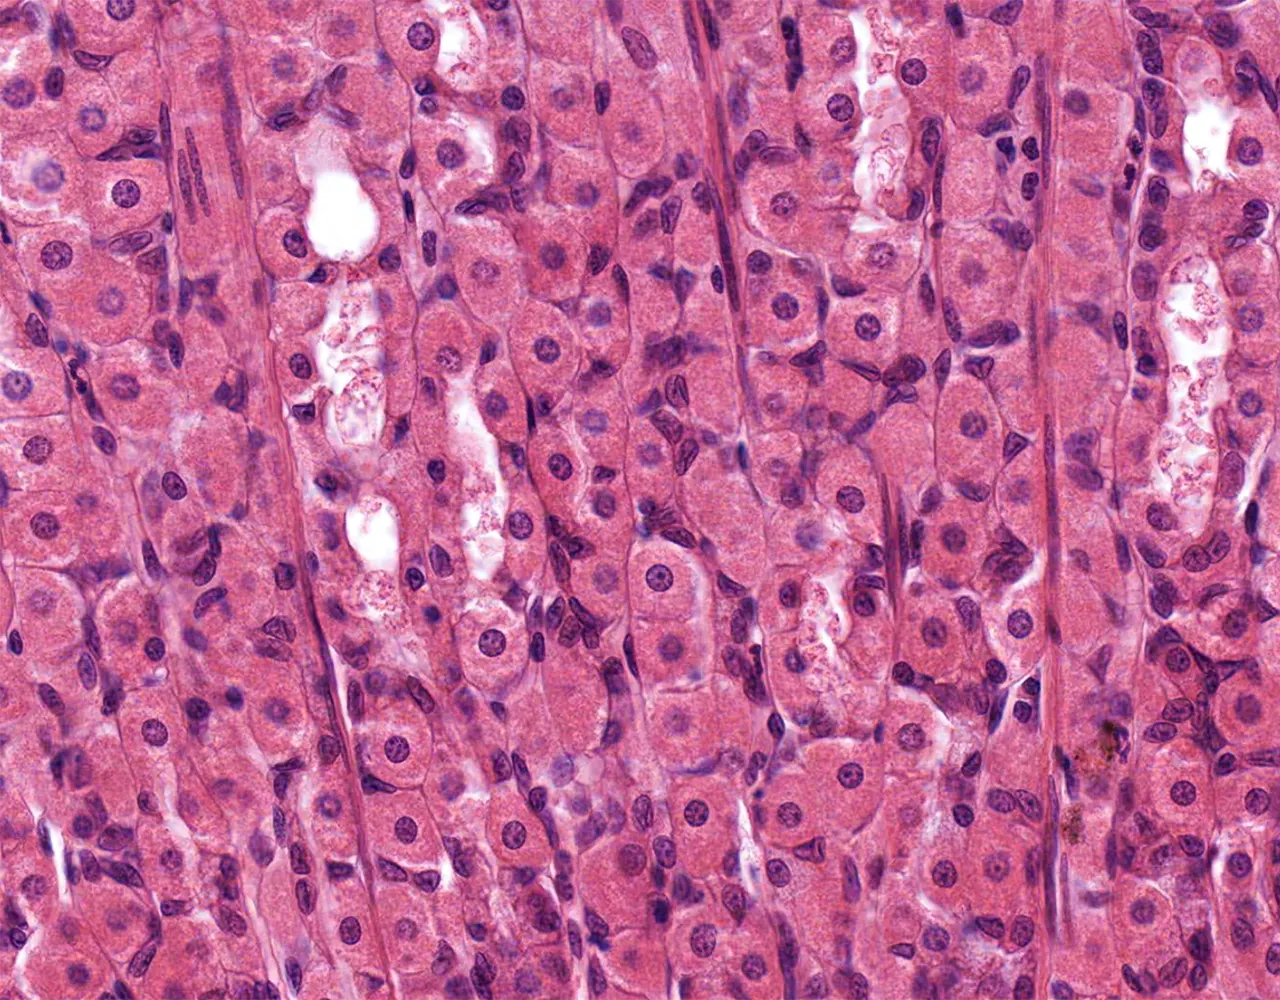

- The wall of the stomach is composed of four layers, from the innermost to the outermost: mucosa, submucosa, muscularis propria, and serosa.